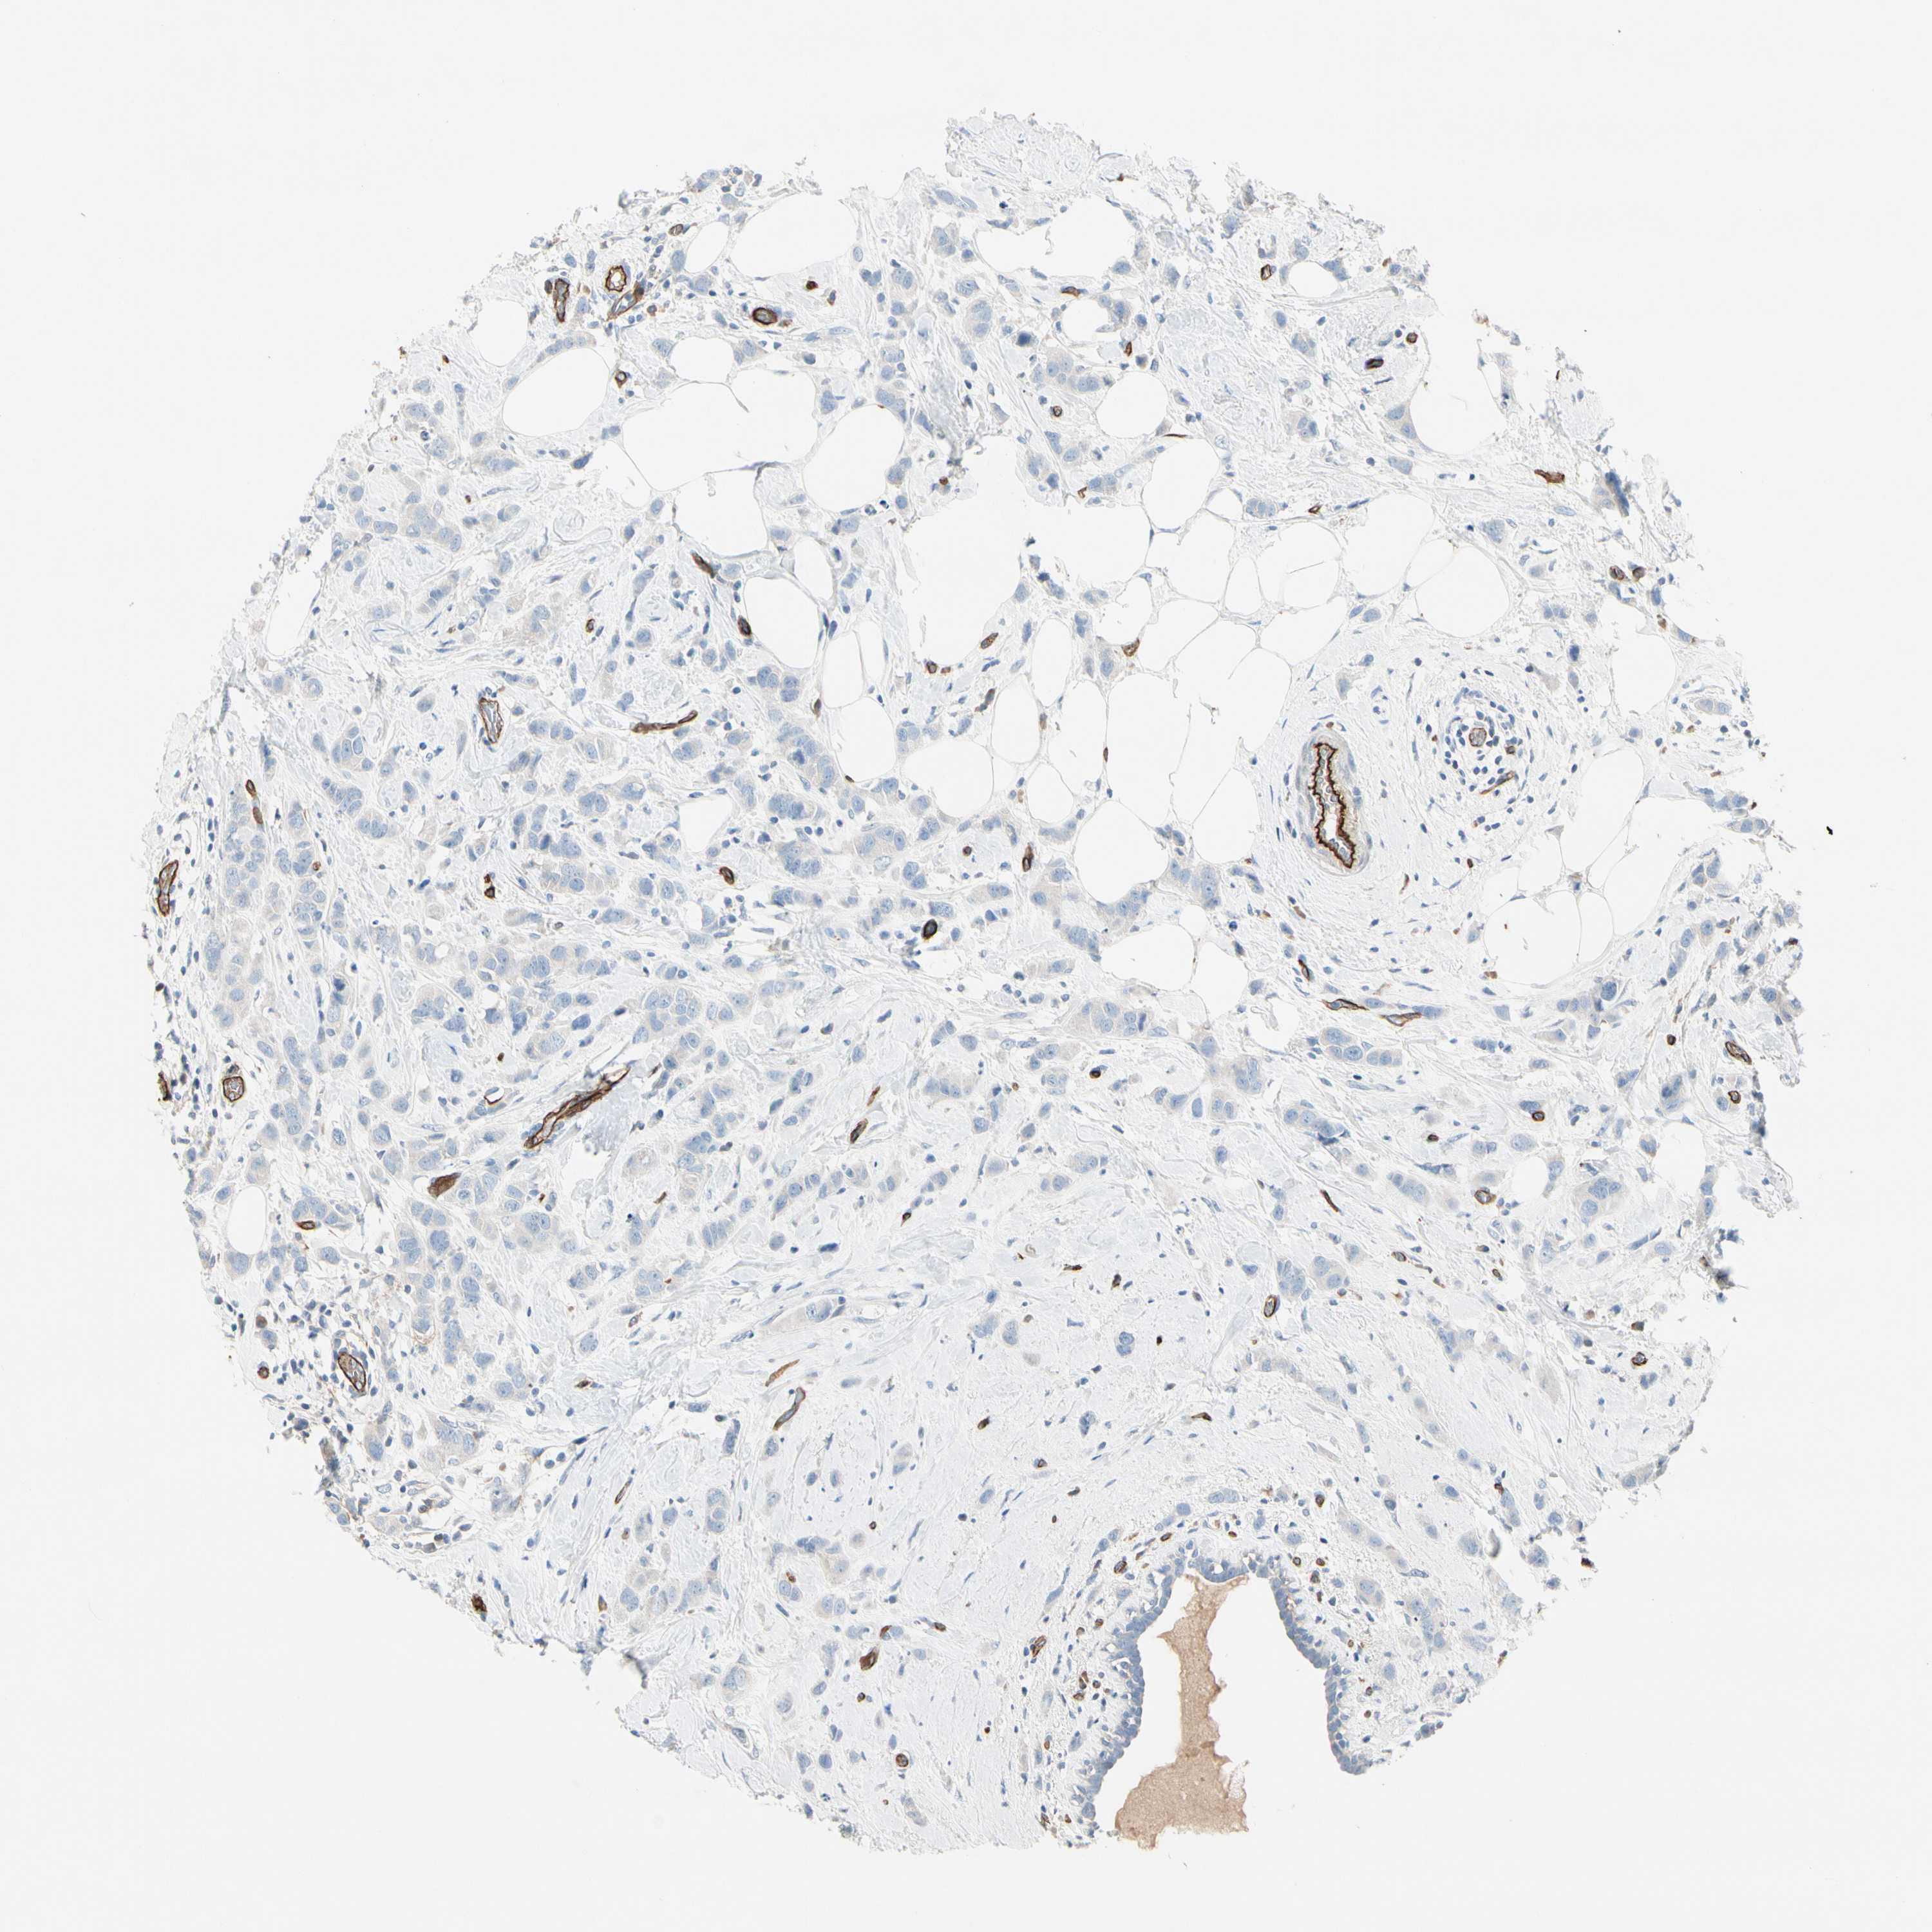

Breast cancer

Human cancer